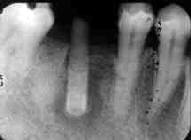

初診時 パノラマ 「7インプラント部拡大

66歳 女性 インプラント体が沈み込んで下歯槽管に近接

数少ない残存歯に高そうな補綴物。清掃状態は不良で歯牙の動揺が著しく、まともに物が 噛める状態ではなかった。インプラントを含む「D6FBridgeは、前歯部との連結部分が破折して 「7インプラントの沈み込みが著しい。その結果、レントゲン的には下歯槽管を突き抜けたような 状態であった。また、初診時には知覚異常は認められなかった。

1年前にも同部が腫れて、インプラントを植立した医院で相談したとのことであるが、その時は 抗生剤を渡されただけとのこと。

下歯槽管(下顎の知覚を司る神経の入った管)に近接しており、このまま放置しておくと 神経を腐らせて生涯知覚麻痺を引き起こす危険性を説いて早急にインプラントを除去する 必要があることを説明。また、手術に際して、一時的に知覚麻痺が起こりうる可能性を 説明して、次回の手術日を決めると同時に抗生剤を投与して消炎を計った.

インプラント体上部に形成された骨を慎重に切除してインプラント体を除去。 心配していた術後の知覚麻痺もなく経過良好。

インプラントを植えて10年以上経過しているとのことであるが、生体の親和性が比較的悪い 材質である反面表面が滑沢な当時の材質では致命的な骨破壊は起こらない。代わりに 周囲の骨を徐々に破壊して沈下する。その際、下歯槽管等は避けるように移動するとも いわれている。従ってインプラント体が直接に触れることは稀ではあるが、除去する際に 神経を傷つける可能性は高いものと思われる。

何と言っても無事に取れてよかった!! それにしても、インプラントを植えた先生! インプラントを植えた後始末は責任をもってやってよ!